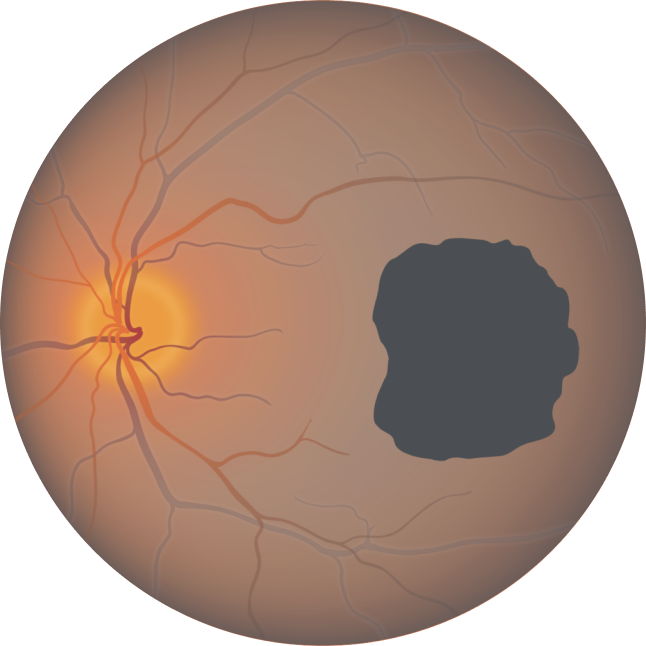

Fundus photograph of a healthy eye

Fundus photograph of an eye with geographic atrophy

Lesion growth may lead to visual decline2,8,9

Baseline Year 1

BCVA 20/63+, GA area 5.18 mm2

Baseline Year 2

BCVA 20/80-2, GA area 10.39 mm2

Baseline Year 5

BCVA 20/200, GA area 18.58 mm2

BCVA = Best-corrected visual acuity.